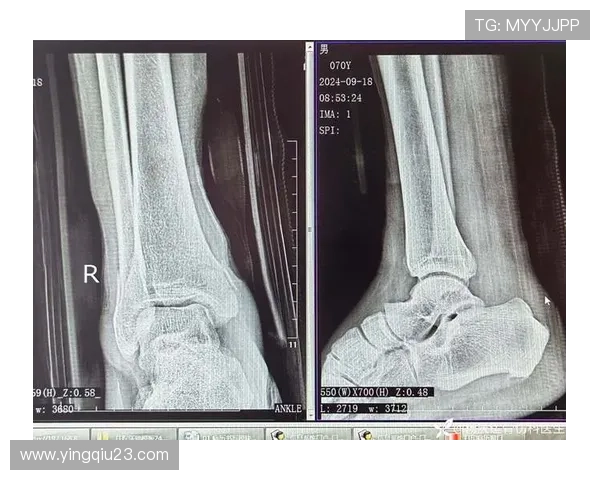

踝关节骨折在足球运动中并不少见,这一伤害往往是由于剧烈碰撞或者不当落地造成的。由于足球比赛中快速变向、急停以及身体对抗频繁,球员们很容易因外力作用导致脚踝部位受伤。而对于职业球员来说,一次严重的踝关节骨折可能意味着整个赛季甚至更长时间无法参赛。

此外,踝关节本身结构复杂,包括多条韧带和多个骨骼,在遭受重创时,其损伤程度也会有所不同。有些球员可能只需经过短暂休养便可复出,但另一些人则可能因为韧带撕裂等情况需要手术治疗。这种情况下,不仅影响了他们的竞技状态,也给心理上带来了巨大的压力。

随着科技的发展,现代医学为运动损伤治疗提供了更多创新的方法和技术,这无疑为众多遭遇踝关节骨折的足球明星打开了新的希望之窗。不少医院已引入先进设备,通过精准影像学检查确定损伤程度,从而制定个性化治疗方案。例如,有些运用干细胞技术加速愈合过程,使得患者能够更快恢复功能。